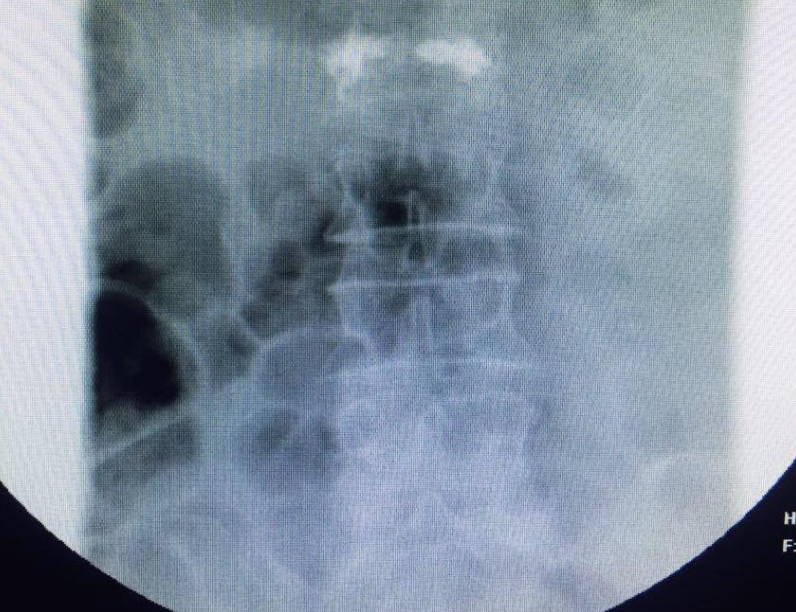

تَمكن قسم جراحة العظام بالمستشفى السعودي الألماني بقيادة الدكتور/ حازم فريد "جراح العمود الفقري" من علاج حالة عمرها 70 عامًا كانت تعاني من كسرٍ إنضغاطي لفقرة قطنية؛ عن طريق الحقن الأسمنتي للفقرات والذي يُعد أحد الوسائل الجديدة فى علاج كسور فقرات العمود الفقرى الناتجة عن هشاشة العظام، حيث يتم علاج هذه الكسور بالحقن وبدون أعراض جانبية تظهر على المريض بعد الحقن.

وأشار الدكتور أنه في الماضي كان يوجد 3 طرق لعلاج كسور العمود الفقرى وهى المسكنات والراحة والحزام الطبى الخارجى، ومازالت هذه الاختيارات الوقائية هى الاختيارات الأولية لتقليل الشعور بعدم الراحة ولكن فى حالة استمرار الآلام الشديدة أصبح متاحًا الآن تحويل المريض إلى طبيب متخصص لتحديد الأسلوب الأمثل لعلاجه ومعرفة مدى ملائمة الحشوة الأسمنتية بالنسبة لحالته وتقوم الحشوة الأسمنتية بتقويم العظام الهشة والتى تقوم بتثبيت العظام المنهارة وهى تحتاج إلى مخدر موضعى فقط دون الحاجة إلى غرفة عمليات ويقوم الطبيب بعمل فتحة صغيرة لإدخال إبرة أو إبرتين لتثبيت العمود الفقرى وتشعر معظم الحالات فى خلال ساعات بتحسن وانخفاض فى الآلام وفى أحسن الحالات يستطيع المرضى استئناف حياتهم الطبيعية خلال 48 ساعة.

وقال إن الوسائل الجديدة والمتطورة للسيطرة على آلام العمود الفقرى تتمثل فى الحقن حيث تعتبر طريقة مبتكرة وهى الطريقة اللاجراحية لتخفيض وعلاج آلام العمود الفقرى ويعتبر الحقن أحد الخيارات لخفض آلام أسفل الظهر بعد دورة من الأدوية وبعد إتمام العلاج الطبيعي حيث يتم التدخل الجراحي لعمل حقن إسمنتي للفقرة المنضغطه بعد رد الانضغاط وذلك من خلال جرح صغير جدا لا يتعدي ١ سم، وتتمركز أهمية الحقن في أنه يقوم بتوصيل المخدر أو الستيرويد مباشرة إلى المفاصل والأربطة أو العضلات أو حول الأعصاب والحقن قد يؤدى إلى تخفيض الآلام